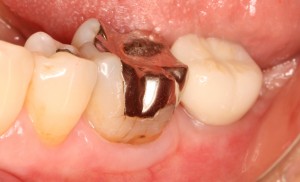

左下奥歯根破折